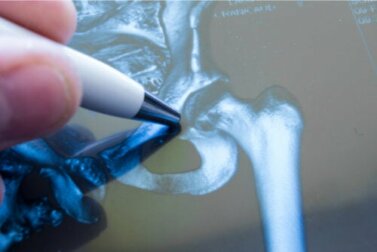

Uma fratura de quadril (FC) é definida como uma lesão e fratura óssea produzida na extremidade proximal do fêmur, conforme indicado pelo Conselho Superior de Pesquisa Científica da Espanha (CSIC). Dependendo da sua localização, pode afetar a cabeça do fêmur, o colo do fêmur, os trocânteres ou outros segmentos.

As fraturas do colo do fêmur são intracapsulares, ou seja, ficam localizadas dentro de uma cápsula articular – neste caso, no ponto de inserção entre o fêmur e a pelve. Enquanto isso, as lesões trocantéricas e em outros segmentos são classificadas como extracapsulares, uma vez que não afetam a articulação em si, mas sim o comprimento do osso.

Depois de uma queda grave, é essencial consultar um médico com urgência, principalmente se a pessoa envolvida for um paciente de idade avançada. O médico fará uma radiografia de emergência para que seja possível observar o alcance da fratura.